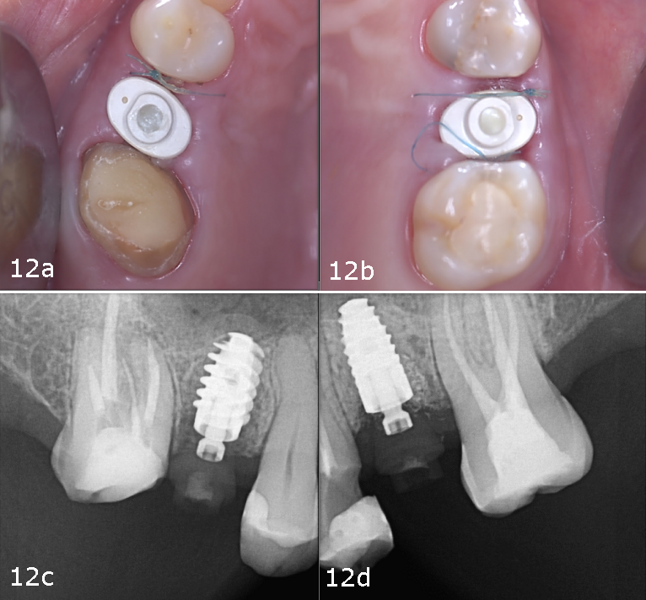

To preserve the ridge contour over time, cerabone plus was hydrated according to the manufacturer’s instructions and placed into the buccal gap at site #25 (Figs. 10a–f). Both sites received healing abutments and were sutured using mesial and distal single interrupted sutures to ensure soft-tissue stability during the healing phase (Figs. 11a–f & Figs. 12a–d). The patient received postoperative instructions along with an analgesic prescription and was scheduled for suture removal after two weeks.